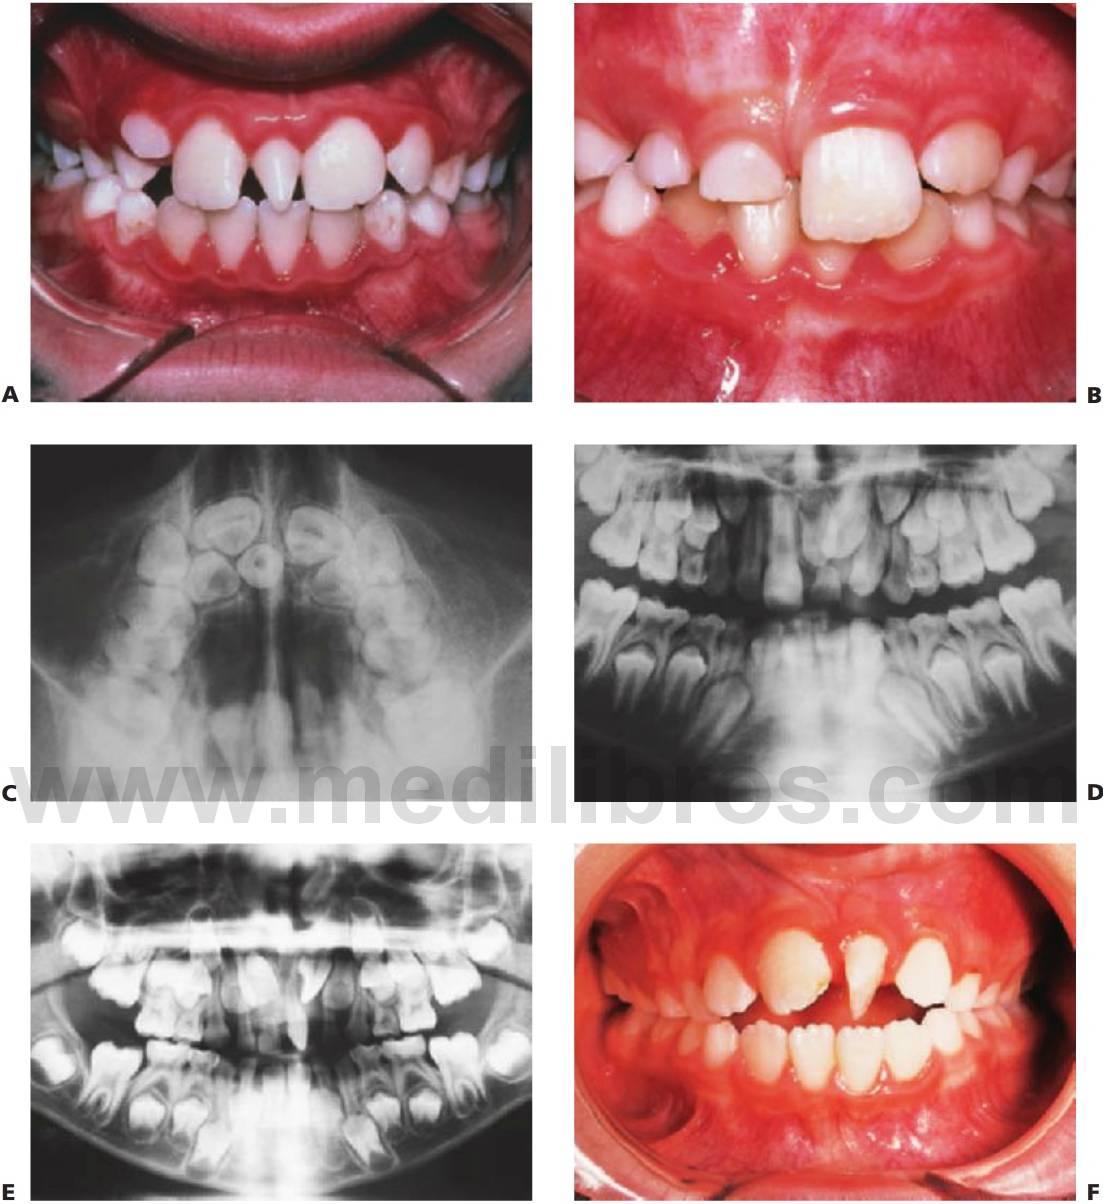

Este trastorno se hereda con un rasgo autosómico dominante y se caracteriza por una frecuencia elevada de mutaciones espontáneas. Se ha localizado en 6p21 con mutaciones en el gen CBFA1 (fig. 9.9).

Manifestaciones

- Estatura corta.

- Aplasia o hipoplasia de una o ambas clavículas (fig. 9.9B).

- Retraso en la osificación de fontanelas y suturas.

- Frente abombada.

- Hipertelorismo e hipoplasia del maxilar superior.

- Huesos wormianos en las suturas craneales.

- Múltiples dientes supernumerarios (fig. 9.9A).

- Retraso en la erupción de los dientes.

- Formación de quistes dentígeros.

- Ausencia o alteración del cemento celular.

Tratamiento

- Diagnóstico precoz y documentación.

- Planificación de la extracción de los dientes temporales no reabsorbidos.

- Remoción quirúrgica de los dientes supernumerarios.

- Exposición quirúrgica de los dientes permanentes.

- Alineación ortodóncica y consideración de una posible cirugía ortognática una vez completado el crecimiento.

Debe observarse que la extracción de la dentición temporal sin exposición quirúrgica de los dientes permanentes no permite la erupción de estos últimos, por lo que se requiere una intervención en dos tiempos. En la primera operación se exponen los segmentos anteriores y se extraen los segmentos anteriores temporales y todos los dientes supernumerarios que pueda haber. Se exponen quirúrgicamente los dientes permanentes, ya sea mediante colgajos reposicionados apicalmente o mediante cadenas de oro cementadas para la tracción ortodóncica.

A continuación, los dientes anteriores se alinean ortodóncicamente. En la segunda operación se extraen los molares temporales, se extraen quirúrgicamente los dientes supernumerarios restantes y se exponen los premolares y molares en los segmentos bucales. Posteriormente se procede al tratamiento ortodóncico definitivo y puede requerirse la realización de una cirugía ortognática en los casos de maloclusión de clase III esquelética grave. Resulta evidente que el tratamiento es muy prolongado en el tiempo y el odontólogo debe valorar los problemas potenciales relacionados con el cumplimiento del tratamiento por parte del niño.